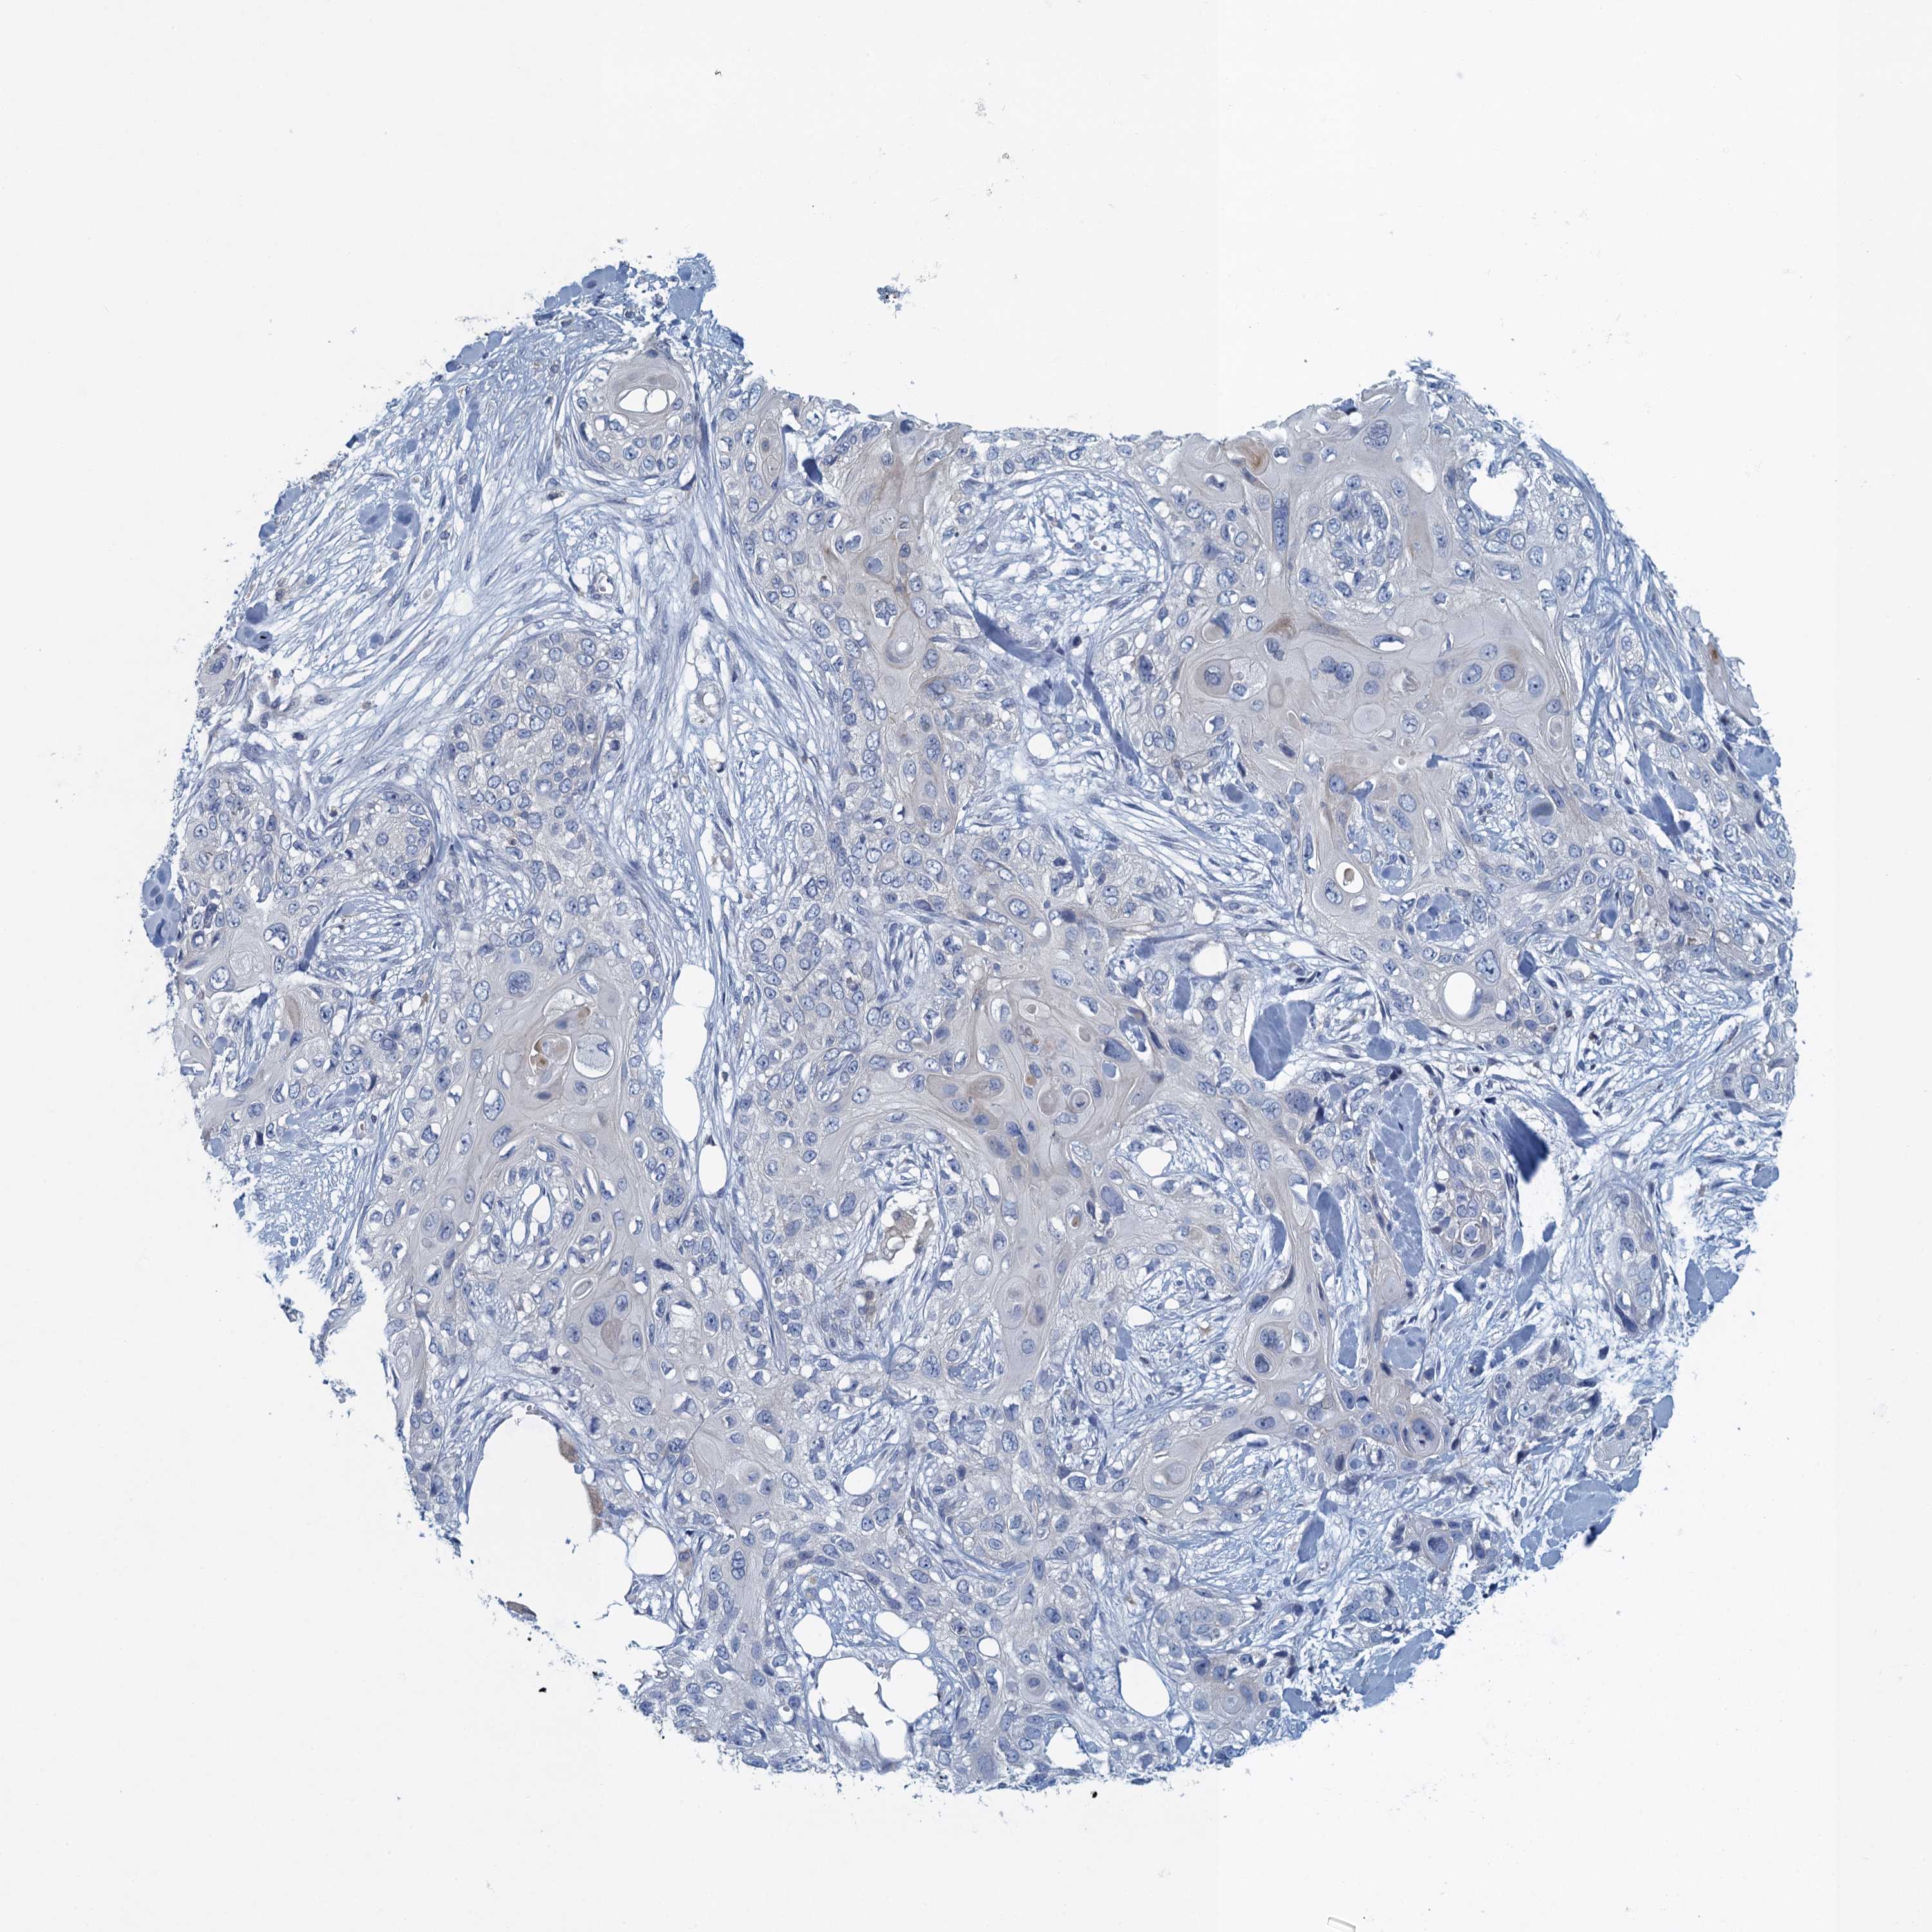

Basal cell and squamous cell cancer

SKIN CANCER - Protein expressioni

A mouse-over function shows sample information and annotation data. Click on an image to view it in a full screen mode. Samples can be filtered based on level of antibody staining by selecting one or several of the following categories: high, medium, low and not detected. The assay and annotation is described here.

Each image is clickable and will lead to virtual microscopy that enables deeper exploration of all samples and also displays staining intensity scores, fraction scores and subcellular localization as well as patient and tissue information for each sample.

Antibody HPA039490

Antibody HPA040772

Staining

High

Medium

Low

Not detected

Intensity

Strong

Moderate

Weak

Negative

Quantity

>75%

75%-25%

<25%

None

Location

Nuclear

Cytoplasmic/membranous

Cytoplasmic/membranous,nuclear

Basal cell carcinoma

Squamous cell carcinoma, NOS

Squamous cell carcinoma, metastatic, NOS